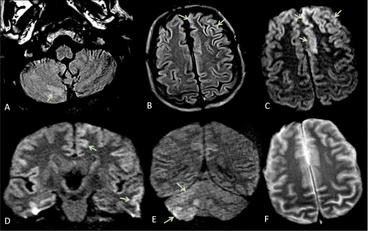

Febbre e tosse non sono i soli sintomi precoci da Coronavirus: quelli neurologici sembrerebbero davvero importanti per una diagnosi tempestiva

9 aprile 2020 - Il Covid-19 spaventa l’intero mondo e i ricercatori lo studiano senza sosta nel tentativo di trovare una cura adeguata. Moltissime infezioni virali possono danneggiare gravemente la struttura e la funzionalità del sistema nervoso causando patologie come encefalite centrale, encefalopatia tossica e gravi lesioni demielinizzanti. Con l'attuale pandemia Covid-19, risulta quindi molto importante sensibilizzare i medici a considerare l'impatto che Covid-19 potrebbe avere sul sistema nervoso centrale. Nella ricerca che troviamo al link sottostante è riportato che oltre ai sintomi sistemici e respiratori, il 36,4 per cento dei pazienti con Covid-19 sviluppa sintomi neurologici precoci come mal di testa, disturbi di coscienza e parestesia. Il lavoro citato conclude quindi ipotizzando che i pazienti con infezioni da Covid-19 devono essere valutati per la possibile presenza di sintomi neurologici. Un’analisi tempestiva del liquido cerebrospinale e la consapevolezza e la gestione delle complicanze neurologiche correlate all'infezione potrebbero quindi risultare fondamentali per migliorare la prognosi dei pazienti critici.

Link

Consapevolezza e gestione accurata delle complicanze neurologiche decisive per i pazienti affetti da Coronavirus